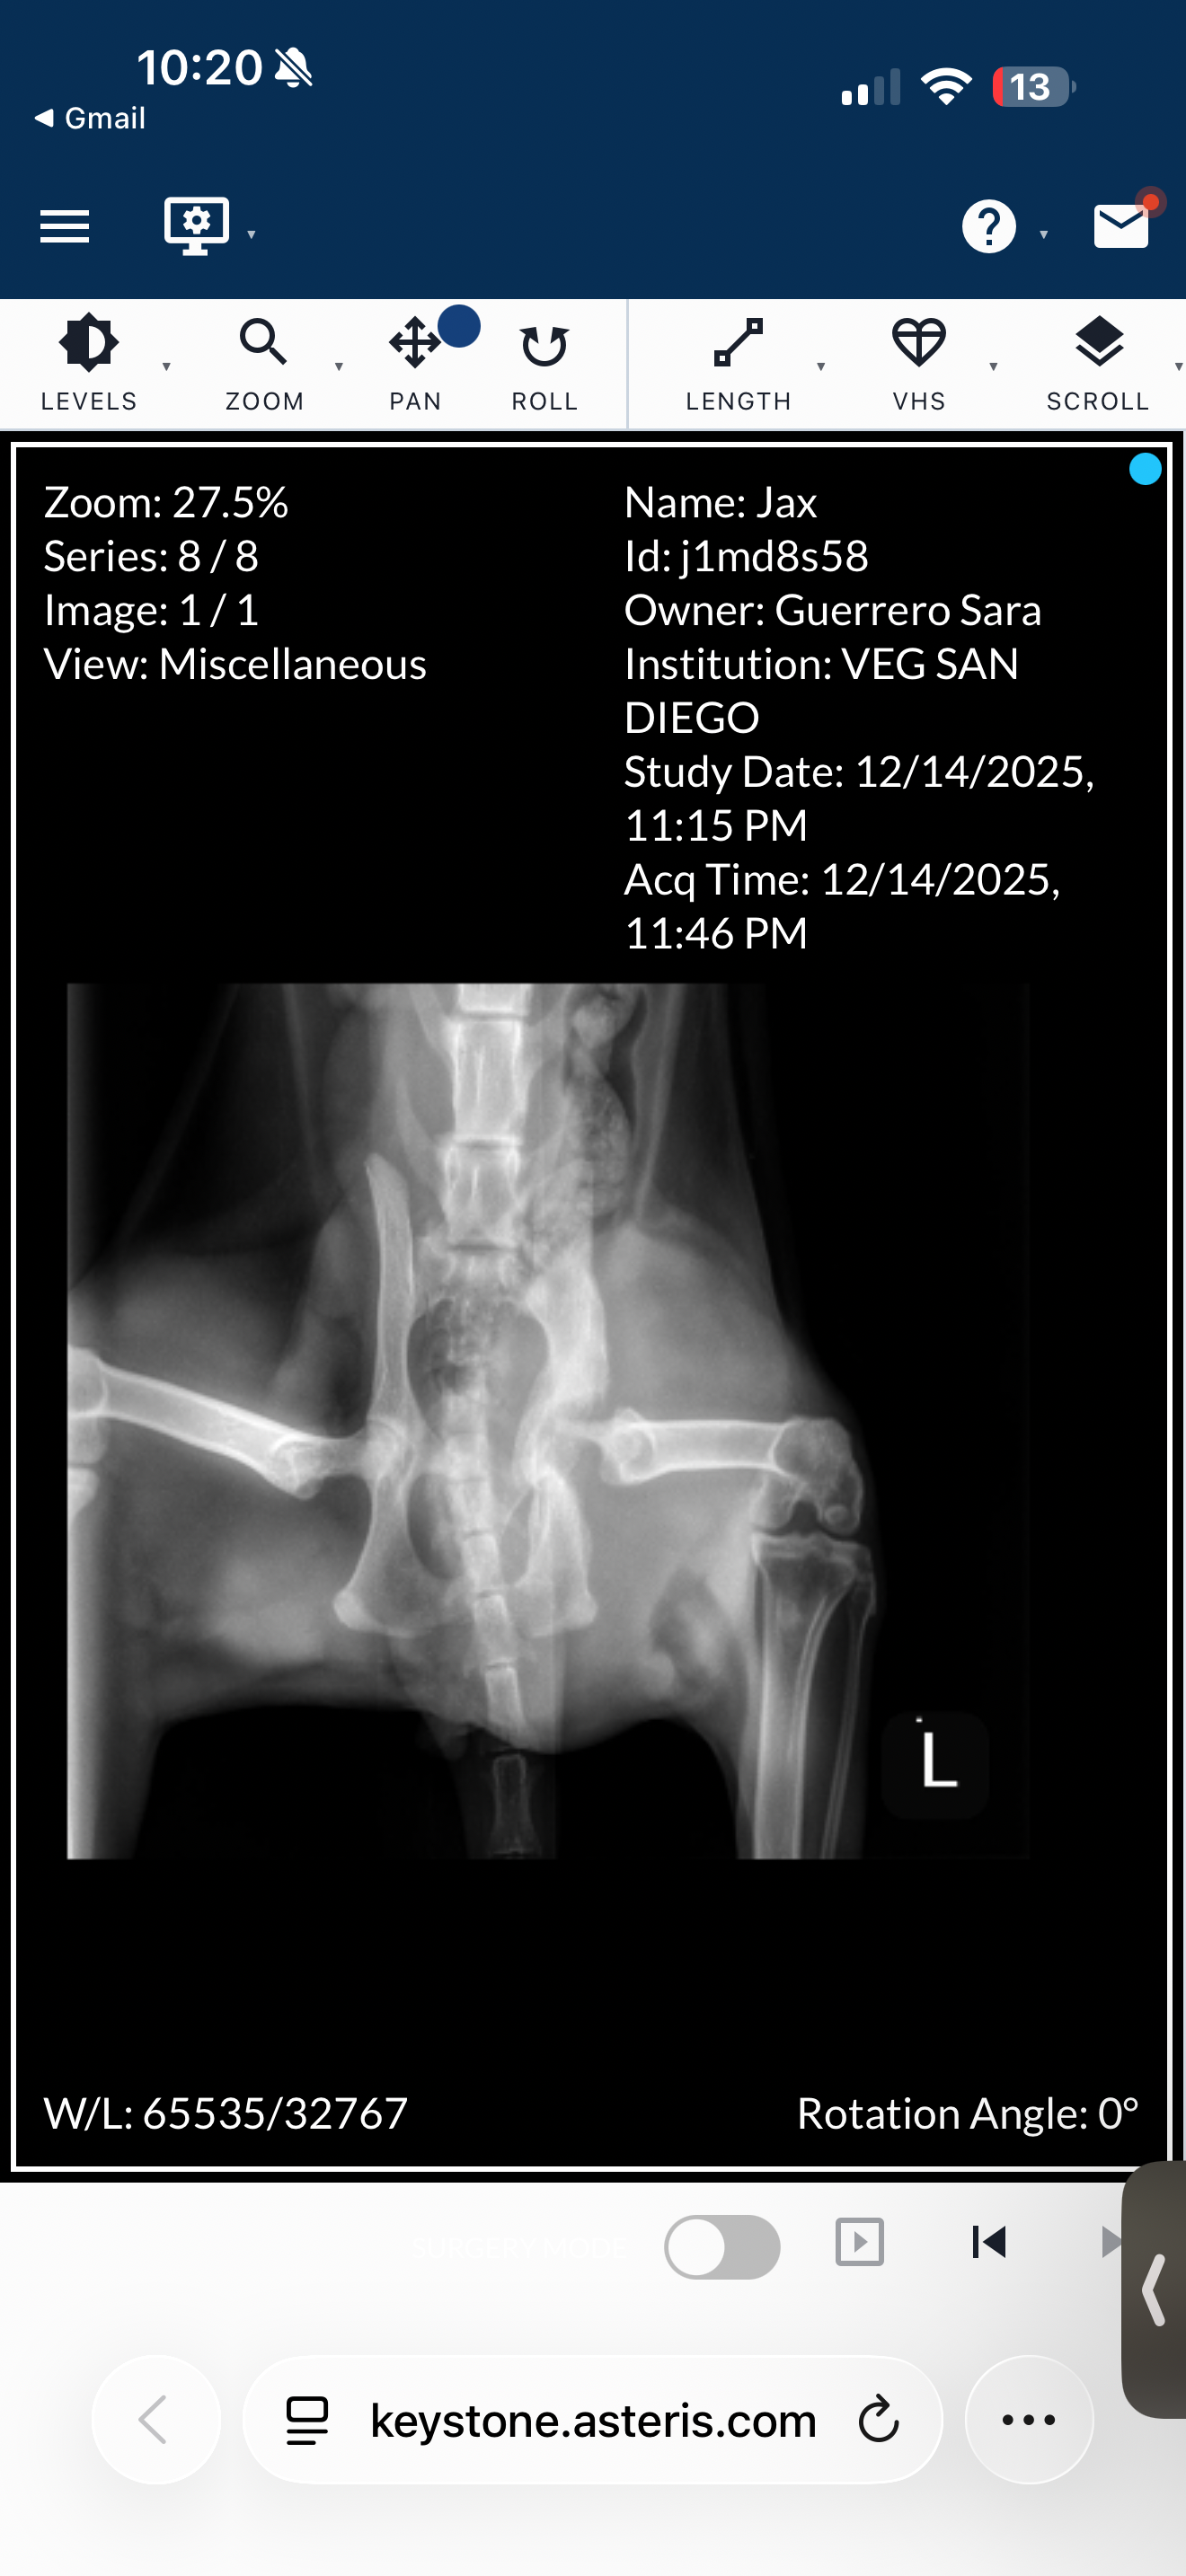

Recently, at the beginning of December, we noticed he had a limp on his left leg. We didn't think much of it, maybe it was a sprain. But we took him to the vet to see what it could've been, and unfortunately, we couldn't afford his x-rays or blood work on that vet-scheduled day. On Sunday, December 14th, we had to take him to the Vet ER and have him seen immediately as he has not been eating, walking, peeing, or doing anything and has just been super sleepy and not active. We finally got his x-rays done and blood work. I show some x-ray pictures and his leg isn't looking too good. They found an abscess in his leg that we need to be able to remove, and the vets are also suggesting leg amputation, but the cost of that surgery would be close to $7,000-$8,000. Just to get him seen and all of the x-rays done at the ER, we have already paid close to $2,000. We unfortunately cannot afford this surgery and without the surgery, we have to put him down. That night was very upsetting and confusing for me and my partner. We had to think about putting him down because we wouldn't be able to financially get his surgery. So, I am asking for the littlest help from anyone, please, so we can at least try to save his life. He is only so young, and we are deciding between the help he needs or not helping him for financial reasons.